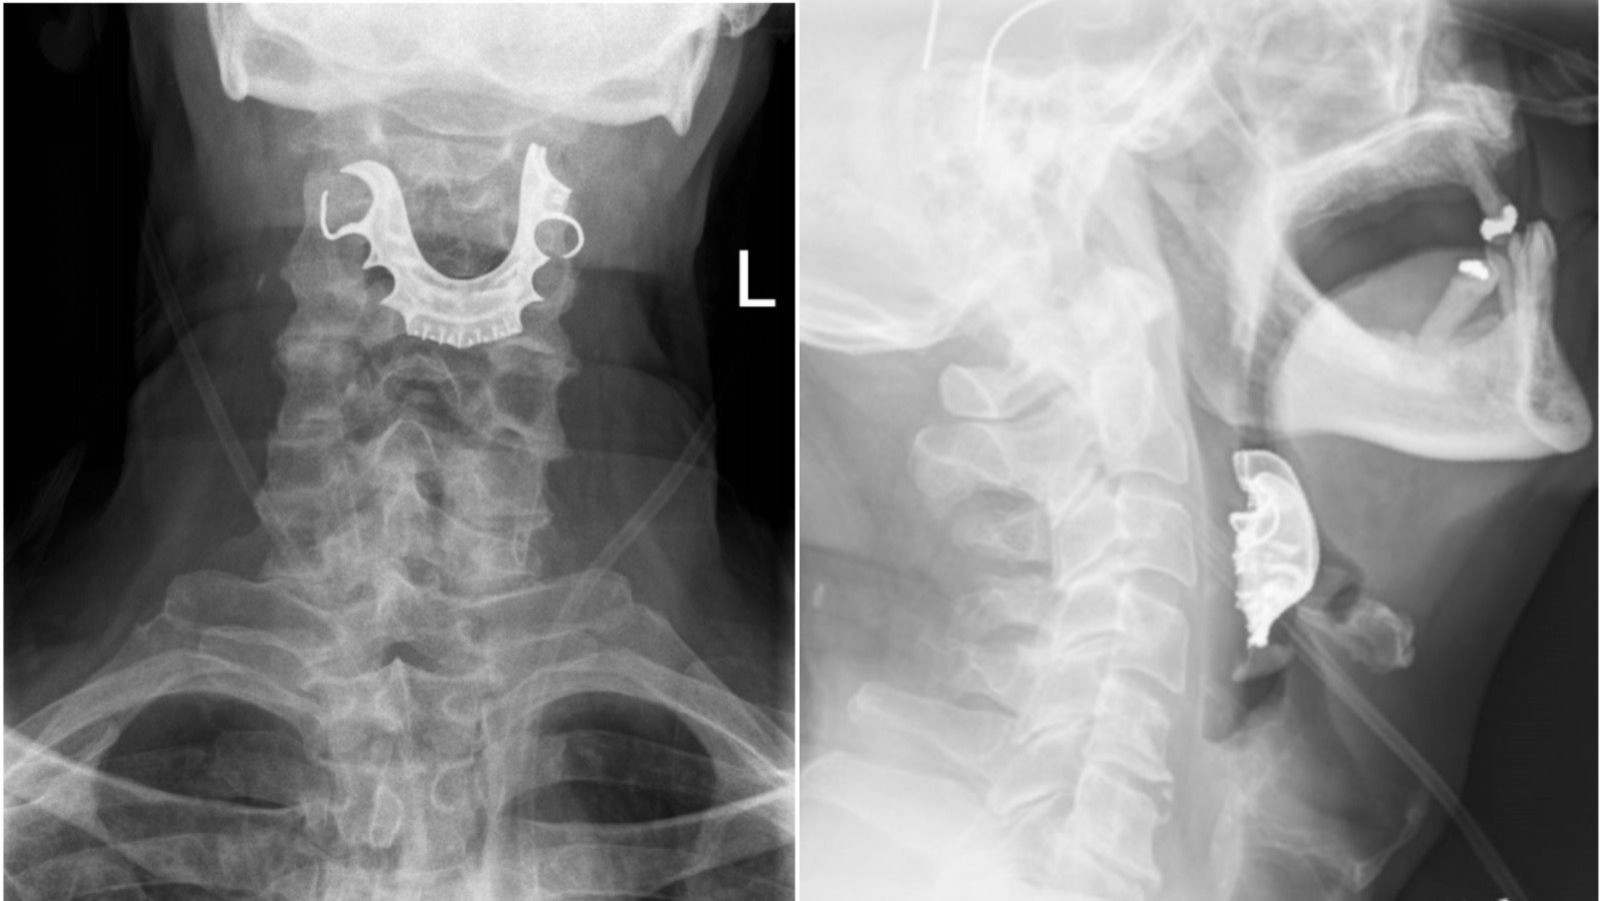

Radiografiile au demonstrat că această proteză rămăsese blocată în gât. Bărbatul a fost operat de urgenţă pentru îndepărtarea obiectului şi a fost externat după şase zile.